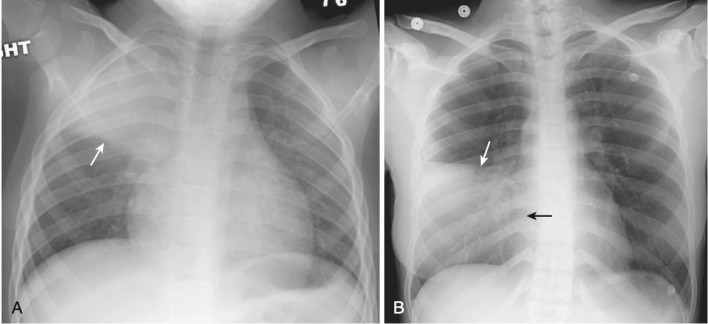

- Một số viêm phổi, chủ yếu ở trẻ em, có thể có hình cầu trên phim chụp X quang phổi.

- Những viêm phổi tròn này hầu như luôn nằm sau phổi, thường là ở các thùy dưới.

- Các tác nhân gây bệnh bao gồm Haemophilus influenzae, Streptococcus và Pneumococcus.

- Viêm phổi tròn có thể bị nhầm lẫn với một khối u ngoại trừ các triệu chứng liên quan đến nhiễm trùng thường đi kèm với các phát hiện ở phổi và các khối u không phổ biến ở trẻ em (Hình 6).